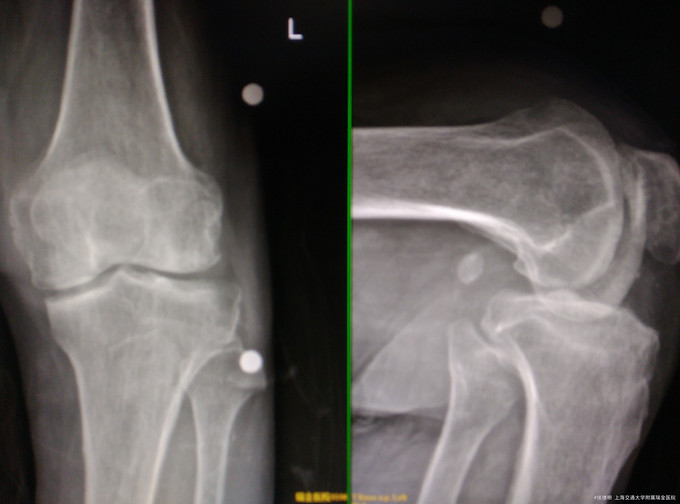

查体、辅查 查体: 神清,精神可,左膝关节轻度内翻畸形,稍肿胀,左膝关节内侧压痛,内外侧稳定性可,侧方应力试验及抽屉试验阴性,膝关节内侧压痛明显 辅查:。X片示膝关节退行性病变,内侧间隙变窄

诊断: 左侧膝关节退行性病变 处理:左侧膝关节单髁置换术